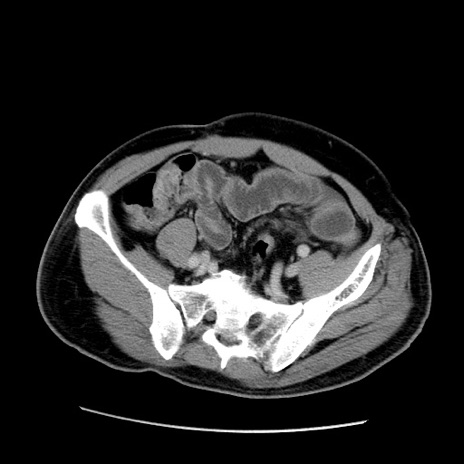

症例22(横断像)

【症例】50歳代男性

【主訴】腹痛

【現病歴】AVMからの被殻出血のため回復期リハ病棟入院中。 本日午後3時頃急に下腹部痛が出現した。

【既往歴】AVM、被殻出血、虫垂炎、高血圧

【身体所見】意識晴明、左半身不全麻痺、会話の理解は良好、36.5°C、腹部:膨隆、全体に板状硬、下腹部正中に圧痛点あり、反跳痛-、筋性防御不明、右下腹部にope scar

【データ】WBC 9400、CRP 0.06